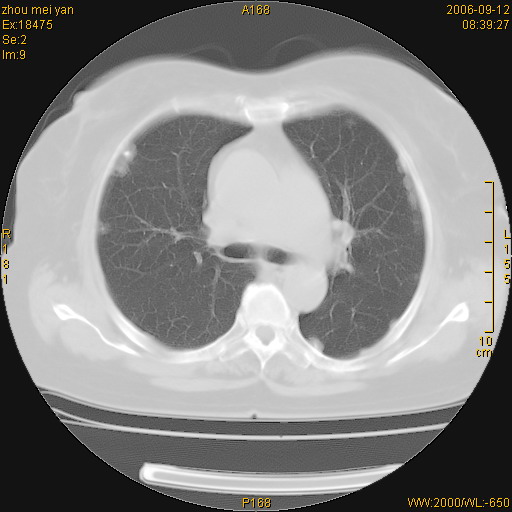

患者、女、55岁。因心率失常住院检查ct发现胸部多发结节。腹部b超肝、胆、胰、脾、肾、子宫附件未见异常。无结核病史,无粉尘接触史。请大家来会诊。谢谢!

病变位于胸膜,多发结节,边界清楚,内见小结节状钙化。其它未见异常。

双侧胸膜多发结节,形态不规则,边缘较清楚,每一个结节中心似乎都有钙化点的特征,与胸膜广基相切。临床无结核病史,无粉尘接触史。

影像表现十分有特点:双侧肋胸膜及膈胸膜广泛散在分布大小在2至6mm左右,较大病灶中心可见钙化。

双侧肋胸膜及膈胸膜广泛散在分布大小不等结节影,较大病灶中心可见钙化。